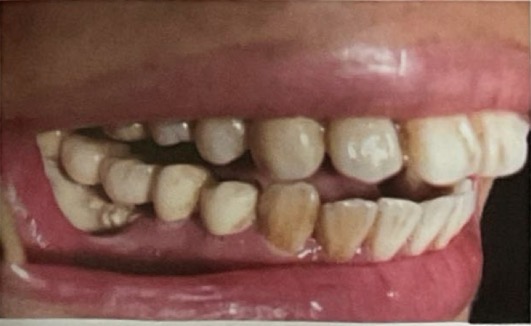

CHẨN ĐOÁN ?

SÂU RĂNG SAU XẠ TRỊ( sâu nhiều răng và lang quanh cổ răng)